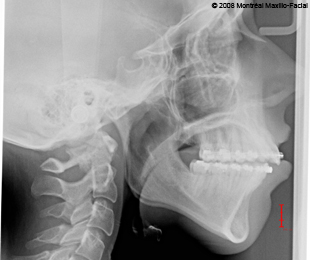

- 13 FÉVRIER 2012 - Rendez-vous avec mon chirurgien pour mes mâchoires

- Photos & radiographies